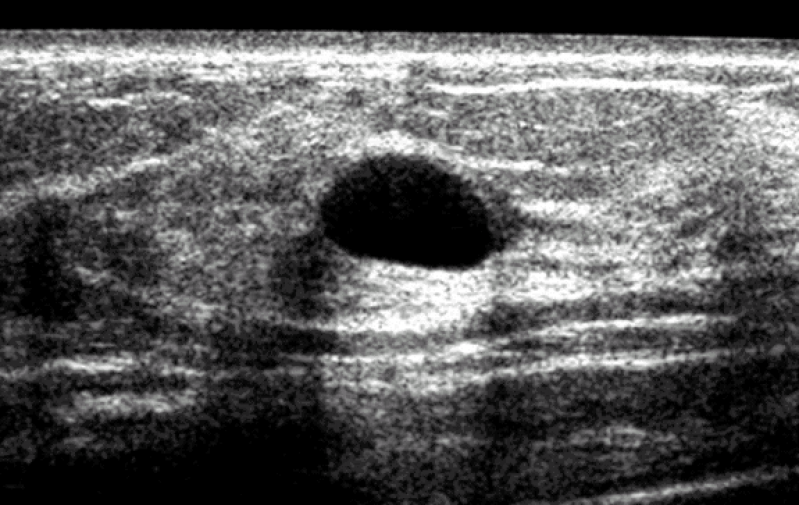

procuro por médico para cisto na mama Pinheiros é fundamental para prevenir, diagnosticar, tratar e reabilitar pacientes com câncer de mama. Além disso, é importante que o procedimento seja feito por um especialista a fim de garantir qualidade e eficiência no resultado. Contudo, vale ressaltar que apenas o autoexame não é suficiente para perceber o surgimento de doenças na região.

A clínica ginecológica é uma especialidade médica que visa a prevenção, diagnóstico e tratamento das doenças relacionadas ao sistema reprodutor feminino. Essa área da medicina é de extrema importância para a saúde e bem-estar da mulher, e a Clinica Bem Estar oferece serviços de qualidade para atender as necessidades ginecológicas de suas pacientes. Com uma equipe de profissionais altamente capacitados e equipamentos de última geração, a Clinica Bem Estar oferece exames preventivos, diagnósticos precisos e tratamentos adequados para diversas patologias ginecológicas. Não deixe sua saúde em segundo plano, entre em contato com a Clinica Bem Estar e solicite uma cotação para cuidar do seu bem mais precioso: a sua saúde.